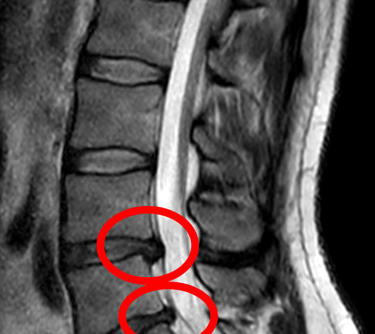

What is a Herniated Disc?

A herniated disc occurs when one of the discs in your spine slips out of place or ruptures, pressing on nearby nerves. This can lead to sharp pain, numbness, or tingling, especially in the back, neck, arms, or legs. Whether from an injury, poor posture, or age-related wear and tear, this common issue can drastically affect your quality of life.